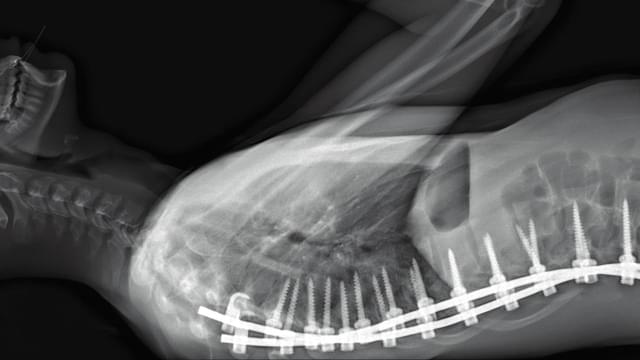

本作は「人体」が最大の関心事となる場所=パリ北部近郊の5つの病院のオペ室を舞台に展開する “21世紀の人体解剖書”。医師視点のカメラや内視鏡の映像を使い、脳や大腸、眼球、男性器など様々な外科手術や帝王切開の模様を医師の視点で見つめる。思わず目をそむけたくなるほどの生々しさと同時に、肉体が持つ生命力や美しさを感じさせてくれる。また、死と隣り合わせの職場での医療従事者たちの心境や、死体安置所でのおくりびと達の仕事ぶりが描かれ、医療とは何か? 肉体と魂とは何か? 人体の神秘と人間の恐怖の根源を探るドキュメンタリーだ。

約30秒の特報予告は、養老孟司氏による推薦コメント「ふだんは見られない手術時の臓器や内視鏡の映像が見られる。これは貴重な体験になると思う」にはじまり、圧倒的な映像体験という宣伝文句に違わぬ本編の一部分を垣間見ることができる。日本版ポスタービジュアルは、岡野登(Cipher.)氏が担当。人体頭部のレントゲン写真がアートのように配置され、本国の監督たちも「素晴らしい!」とその出来に太鼓判を押している。